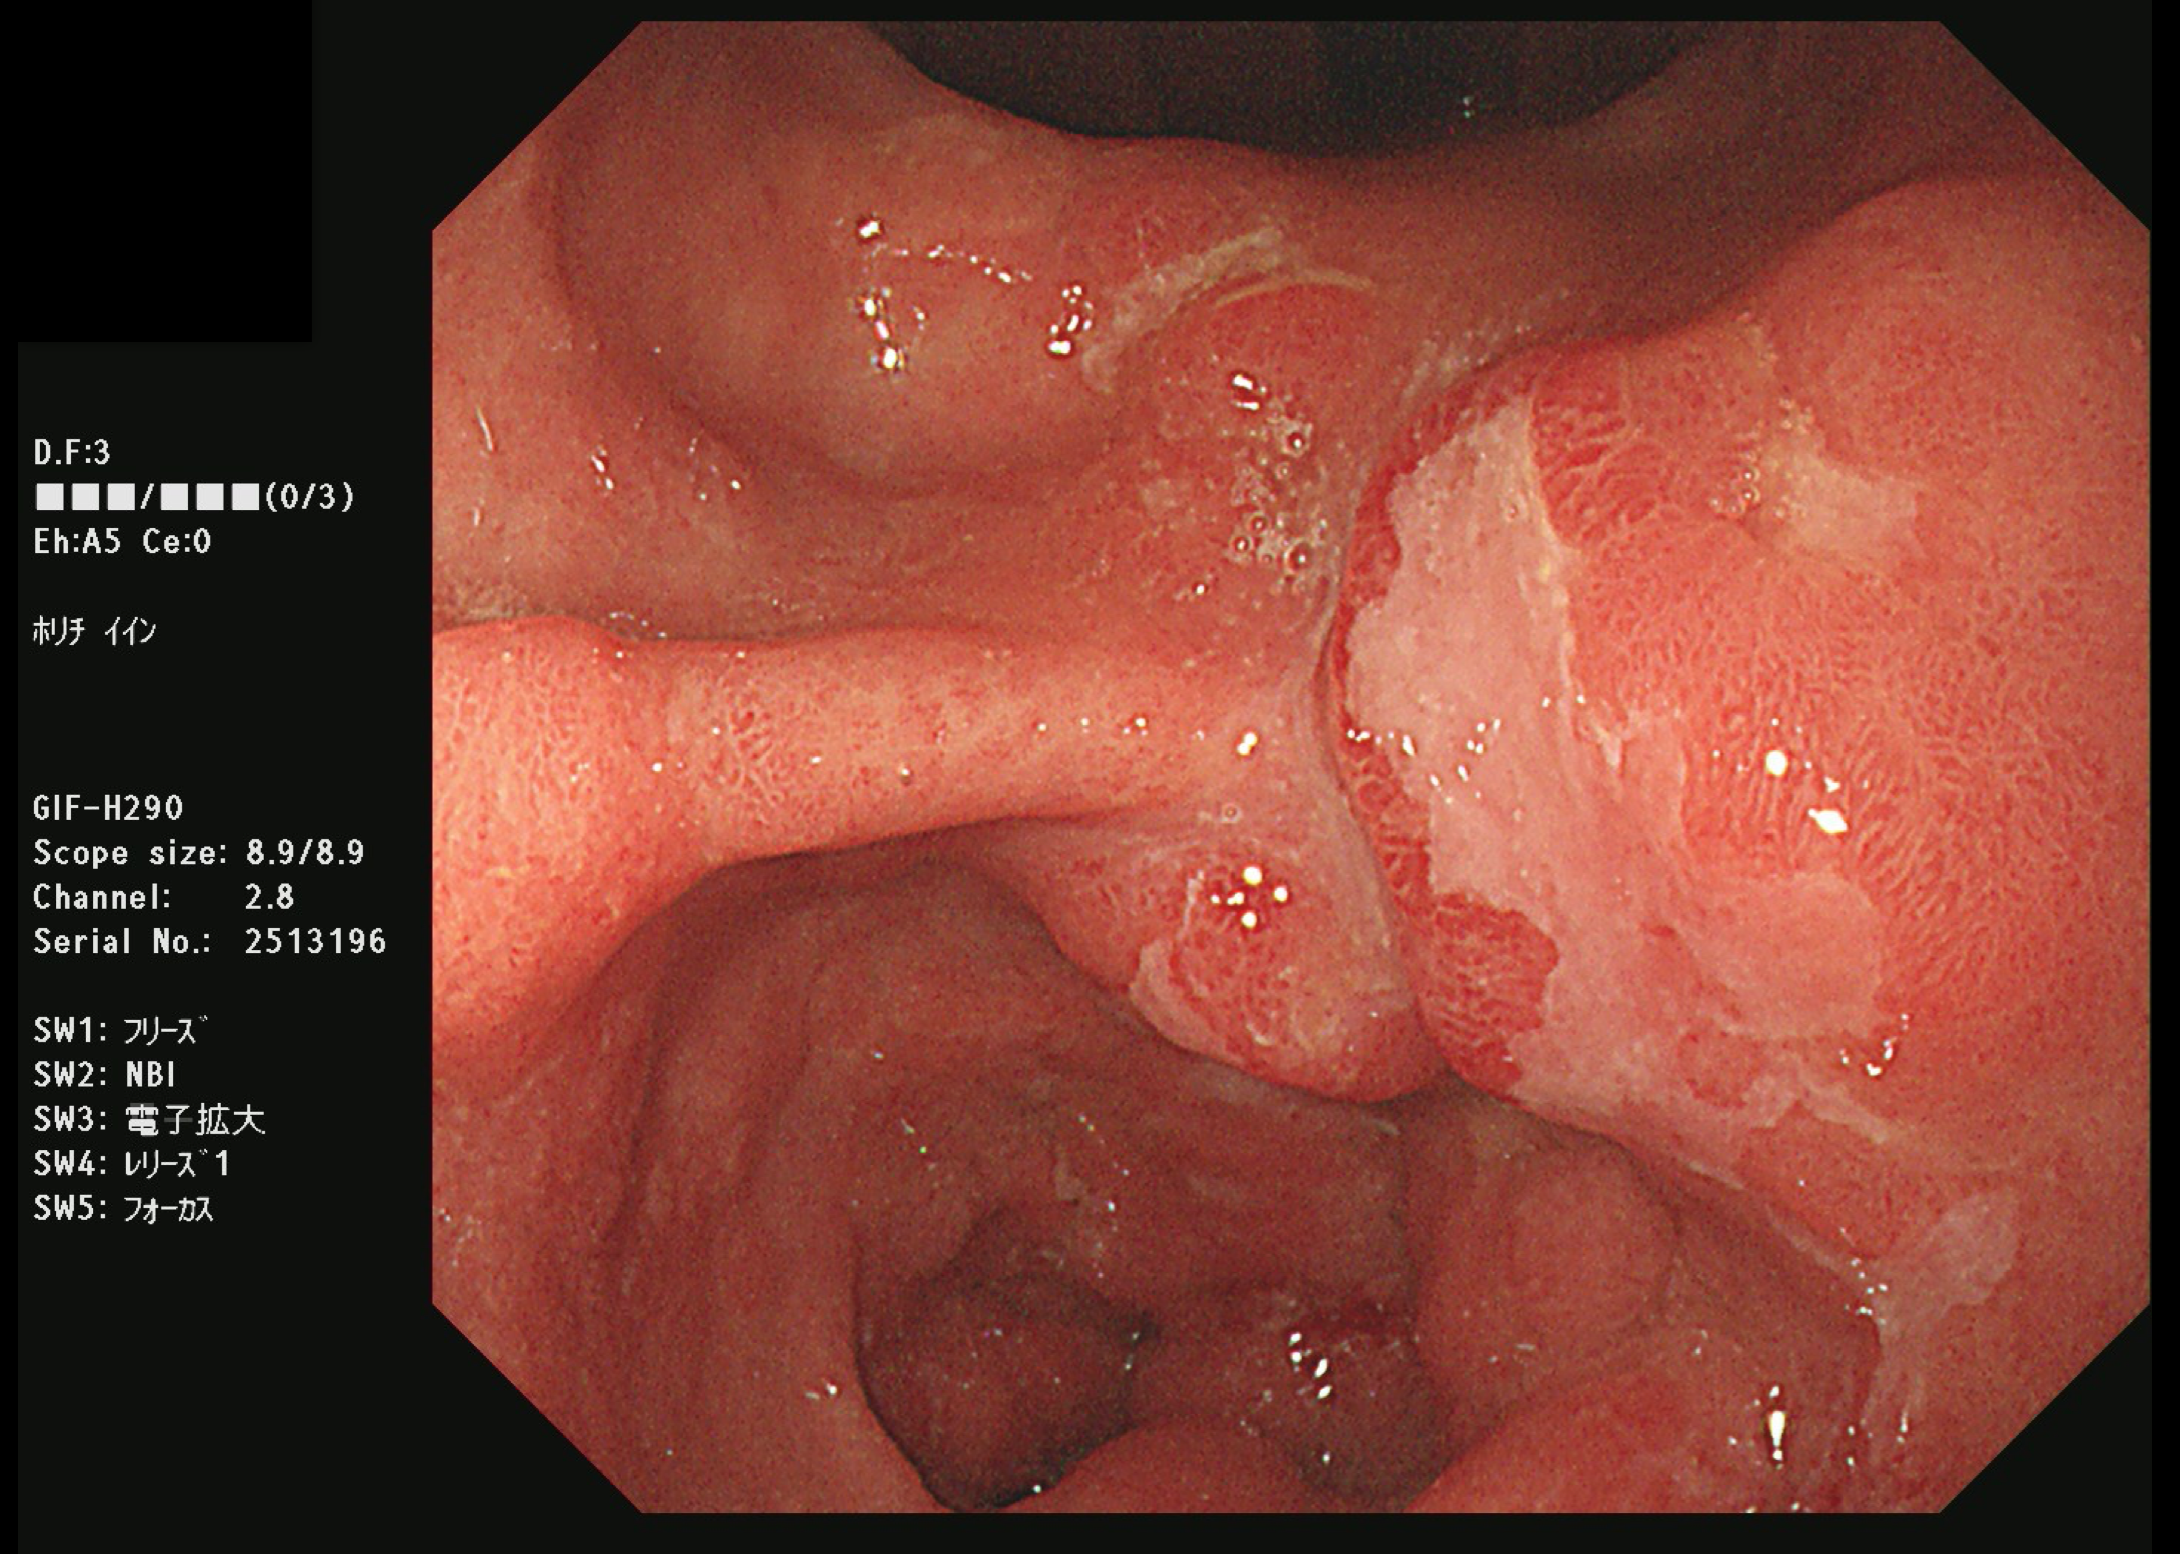

胃がん(上部消化管内視鏡)

食道がん(上部消化管内視鏡)

胃がん検診

富山市の胃がん検診は胃内視鏡(上部消化管内視鏡)もしくは胃透視(バリウムを飲む検査)でおこなわれています。胃がんはかつては日本人にとって非常に多いがんでしたが、ヘリコバクターの保菌者の減少とともに、胃がんも少なくなりつつあります。

胃がん検診では喉頭部・食道・十二指腸上部を観察します。

当院では胃内視鏡(経口)のみを実施しております。胃の中を十分に検査するために高解像度の内視鏡を使用しており、そのため口からの内視鏡検査となります。一般的に鼻からの経鼻内視鏡による検査の方が楽な検査と言われていますが、内視鏡が細い分、最新型の経口高解像度内視鏡に比べて解像度が落ちます。